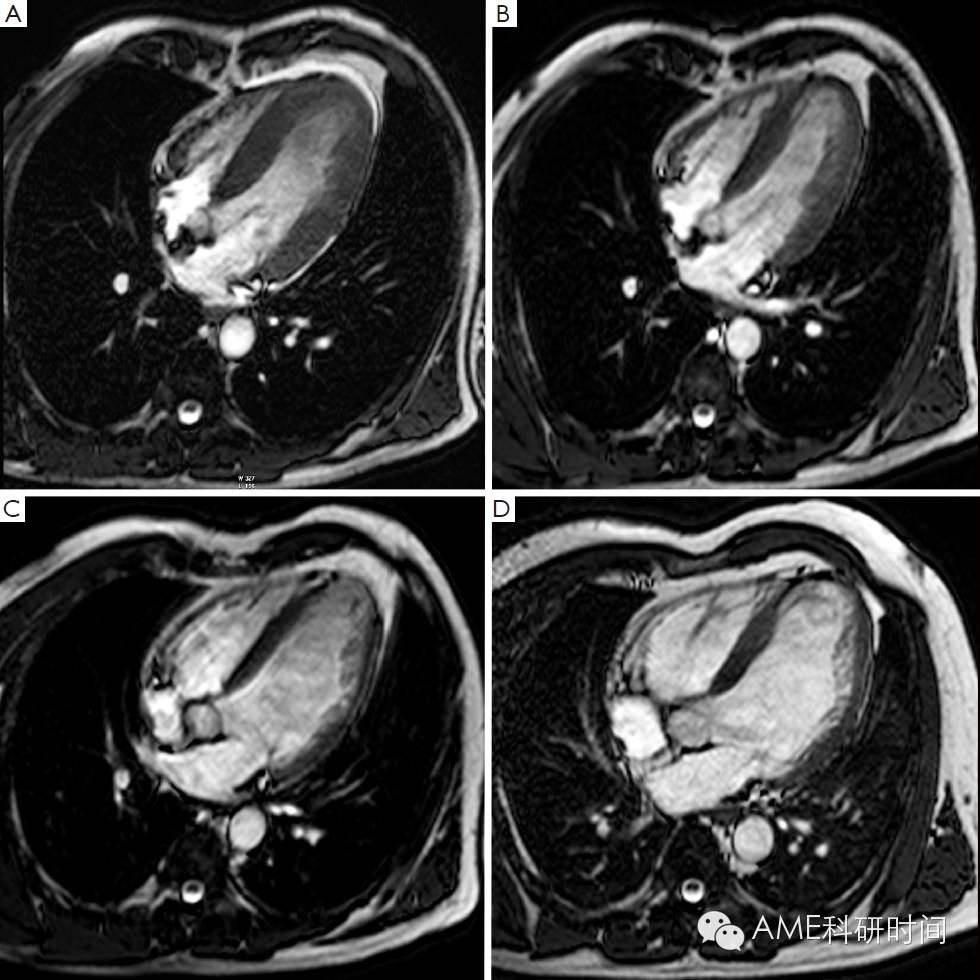

在过去的几年里,越来越多的证据表明,通过短时间反转回复序列(STIR) T2加权像的影像数值,可以判断危险心肌,即在冠状动脉阻塞时可通过再灌注得到挽救的心肌(2)。事实上,T2加权像STIR对组织游离水(水肿)的增加特别敏感,而游离水的增加通常伴随缺血性心肌损伤,无论组织是否坏死(3,4)。心肌水肿(缺血引起ATP依赖的钠钾离子通道的功能紊乱,导致膜两侧钠离子梯度的改变,从而引发细胞内水肿)是缺血性损伤的早期症状,T2加权像STIR成像对于在急诊中患有不稳定型心绞痛和不断发展的心肌梗死患者是一种非常有用的诊断手段(5,6)。尤其是在T2加权像STIR影像中,心肌水肿会呈现出强烈信号(亮)(见图1)。Abdel-Aty等人(7)的最近研究显示,通过水肿造影描绘了在缺血发生后30分钟内及不可逆性心肌损伤[表现为肌钙蛋白水平增高和迟发钆增强(LGE)]前急性心肌损伤的情况。Aletras等人(2)用实验证明了在发生再灌注心肌梗死两天后的T2加权像STIR影像中,水肿的面积对应于在发生冠状动脉阻塞时微球注射所呈现的危险心肌的面积(即参考标准)。此外,危险心肌面积明显大于最终发生梗死的心肌面积,说明在T2加权像STIR影像中呈现的水肿区域同时包括了可逆和不可逆损伤的心肌(即永久性心肌损伤)。最近在再灌注后ST-段抬高的心肌损伤患者中,使用单光子发射计算机断层成像术(SPECT)对这项技术进行检验。在急性心肌梗死7天后,使用经皮冠状动脉介入治疗前,通过99mTc-替曲膦SPECT看到的灌注不足区域与通过T2加权像STIR影像检测到的心肌水肿区域相似(8)。因此,T2加权像STIR成像术能够在不干扰急性期患者诊治的情况下,对危险心肌组织进行准确的、可回顾的和非电离的检测。此外,在急性再灌注心肌梗死的病人中,我们和其他一些研究组证明此技术得到的结果和血管造影术对危险心肌评分结果的一致性(9,10)。然而,最近有人对T2加权像STIR成像描绘危险心肌组织的准确性产生怀疑,因为它具有对人造品固有的高灵敏度和可重复性差(11)。此外,此技术的操作序列导致信噪比低及易于在心内膜和心室腔的边界检测到“血流慢”的假象。重要的是,我们对T2加权像STIR成像所确定的危险心肌组织的认识来源于数量相对较少的试验研究,需要进一步的研究。在这种情况下,产生了更好的序列产生了,例如T2加权稳定态自由旋进造影或T2弛豫时间图(12,13)。众所周知,T2加权异常在急性和亚急性预后阶段表现最明显,但是随梗死诱发的心肌水肿和炎症的再吸收而慢慢退去(8)。因此,T2加权STIR的序列能够将急性和慢性心肌梗死区分开来(14),因为在T2加权STIR成像中前者伴随着心肌水肿,而后者没有显现水肿。最后一点,T2加权STIR成像能够显现再灌注后心肌出血情况。事实确实如此,无再灌注的心肌梗死,一般不会导致出血,而再灌注的梗死不同与此,经常出现由缺血性再灌注引起的严重微血管损伤,从而导致明显的红细胞渗出(15)。活体和尸检研究显示通过检测血红蛋白降解物的顺磁性,T2加权具有辨别心肌内出血的能力,这将缩短T2弛豫的时间(16,17)。因此,水肿的图像显示出血性梗死区域的不均一性,通常呈现低亮度的核心和高亮度的边缘,因此可与非出血性梗死区别开来,因为非出血性梗死呈现亮度均匀的心肌(图2)。对98位患有再灌注ST段抬高的心肌梗死患者研究,发现25%的患者心肌内出血(18)。这些出血性梗死的患者出现更大的梗死面积和透壁性心梗,更大的无复流区和更少的心肌复活。心肌内出血,是独立于初始梗死面积,不利于左心室重塑的因素。之后,Eitel等人(19)研究发现T2加权检测出心肌出血,预测心肌梗死后6个月发生重大心血管疾病。

图1 Edema imaging in a patient with a reperfused acute anteroseptal myocardial infarction (day 3 post MI). Short-axis T2-weighted STIR imaging at 4 levels (A-D). The jeopardized, edematous myocardium is visible as the myocardium showing increased signal intensity (arrowheads, A-C). Note the extension of the edema towards the adjacent RV anterior wall (arrows, A-D). Adapted from Ischemic Heart Disease by Bogaert J and Dymarkowski S, in Clinical Cardiac MRI Second Edition, Bogaert J, Dymarkowski S, Taylor AM, Muthurangu V (eds). Springer Heidelberg, Germany (ISBN 978-3-642-23034-9).